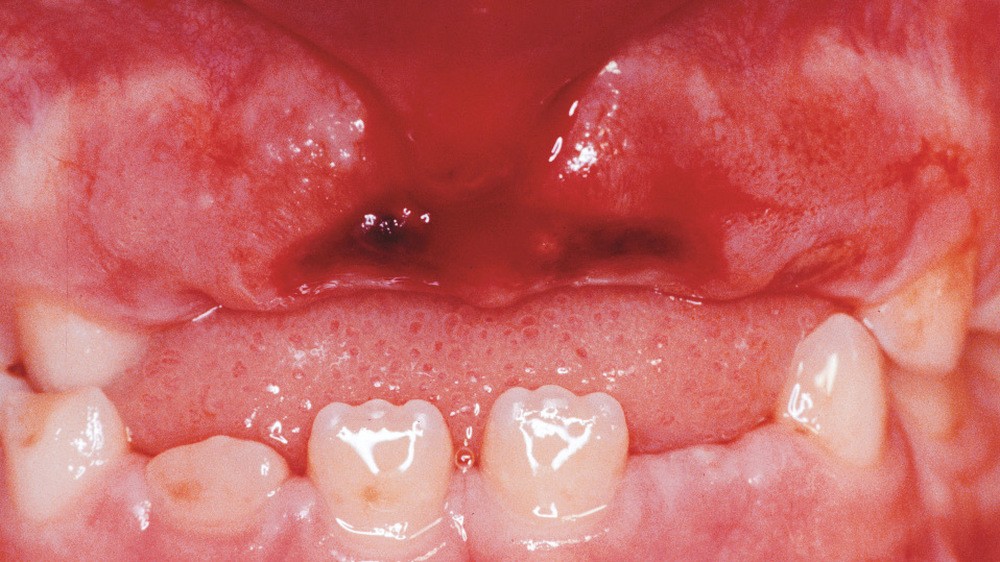

Ils surviennent le plus souvent entre 7 et 10 ans [7], du fait de la laxité du ligament parodontal et de l’immaturité radiculaire (fig. 1).